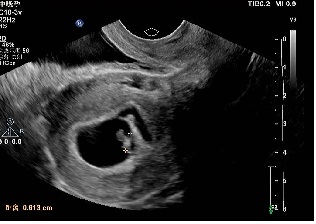

2019年10月18日一超:宫腔内见胚囊,大小17´21´22mm,胚芽长6mm,胎心136次/分。血β-HCG 56778.4、孕酮27.35、雌二醇 373.12。